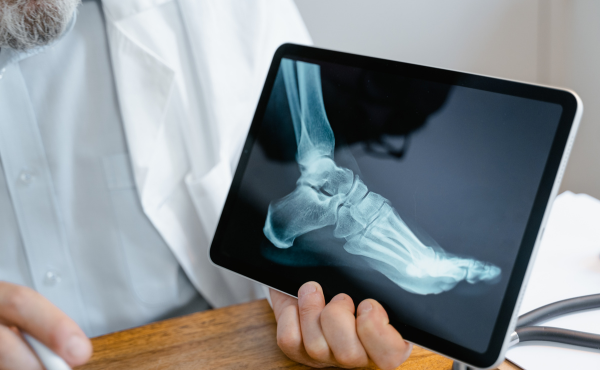

X-Ray Services at Purva Hospital

An X-ray is a quick, painless imaging test that helps doctors view the inside of your body, primarily your bones, joints, and certain soft tissues. It uses a small dose of radiation to capture detailed images, assisting in diagnosing injuries, fractures, infections, and medical conditions.

Bone & Joint X-Ray – For fractures, dislocations, arthritis, and joint pain assessment.